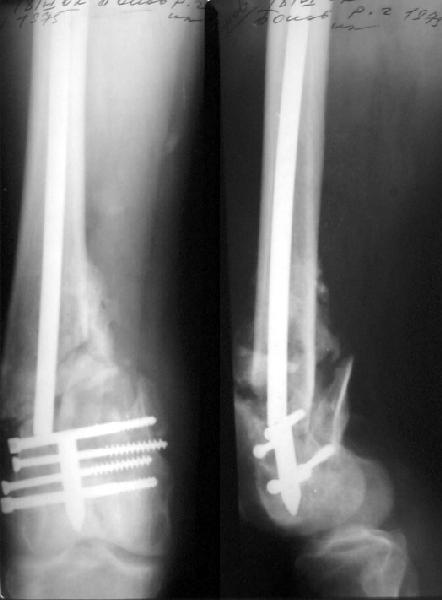

You have done a very good work with your hardware.

If we should look for "hairs in an egg", we can see that distal fragment is a little flexed and (perhaps) valgus.

First deviation could be corrected by removing at first the screw with black arrow.

Another little imperfection is the small size of the nail and large holes (see the other black arrows) just on the fracture line : these mechanically make the nail less resistant and, if weigh bearing is full, they could be a cause of failure.

If your patient will be prudent, fracture will heal very well.